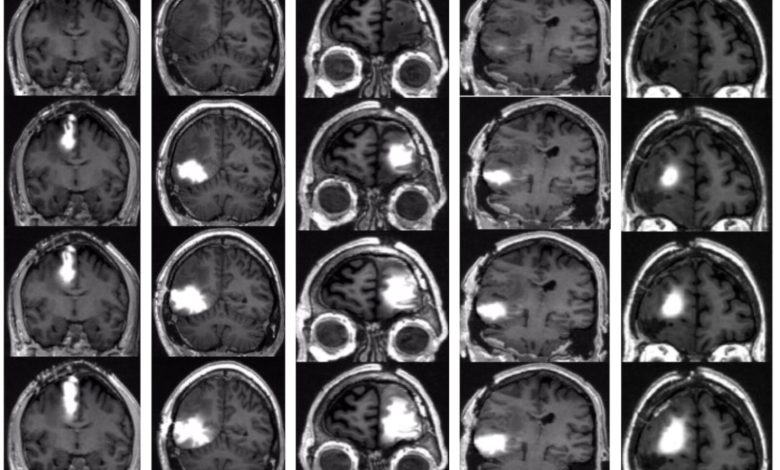

Os exames de ressonância magnética mostram que a quimioterapia administrada pela bomba satura a área dentro e ao redor do tumor cerebral de cada paciente. As imagens superiores mostram o cérebro antes do tratamento; as imagens inferiores foram tiradas 14, 24 e 48 horas após o início do tratamento. Crédito: Jeffrey Bruce, Columbia University Irving Medical Center.

Nenhum dos pacientes apresentou complicações neurológicas graves. E exames de ressonância magnética mostraram que a quimioterapia havia saturado a área dentro e ao redor do tumor.